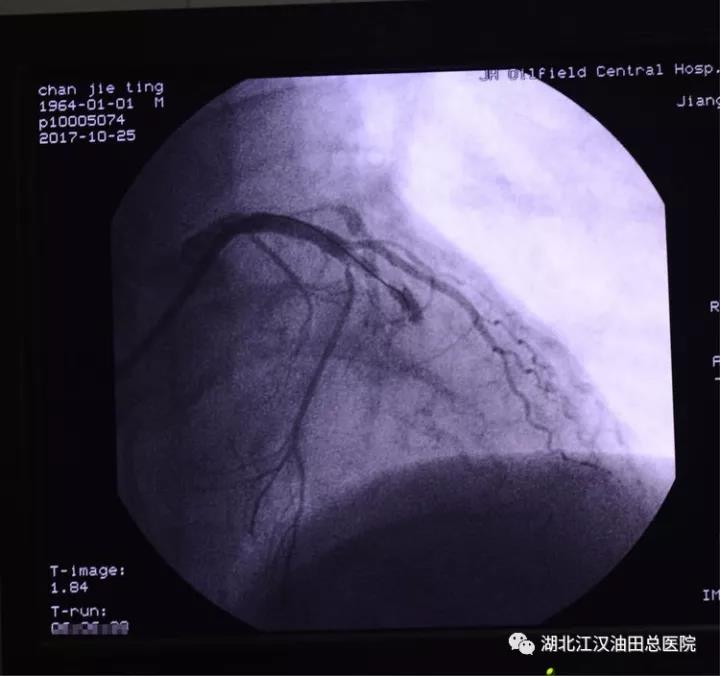

5:56分,心脏血管造影结束,诊断为左前降支血管闭塞。马上开通闭塞血管,植入支架。

6:10分,支架安装完毕,闭塞的血管血流恢复,心肌将重新得到灌注。